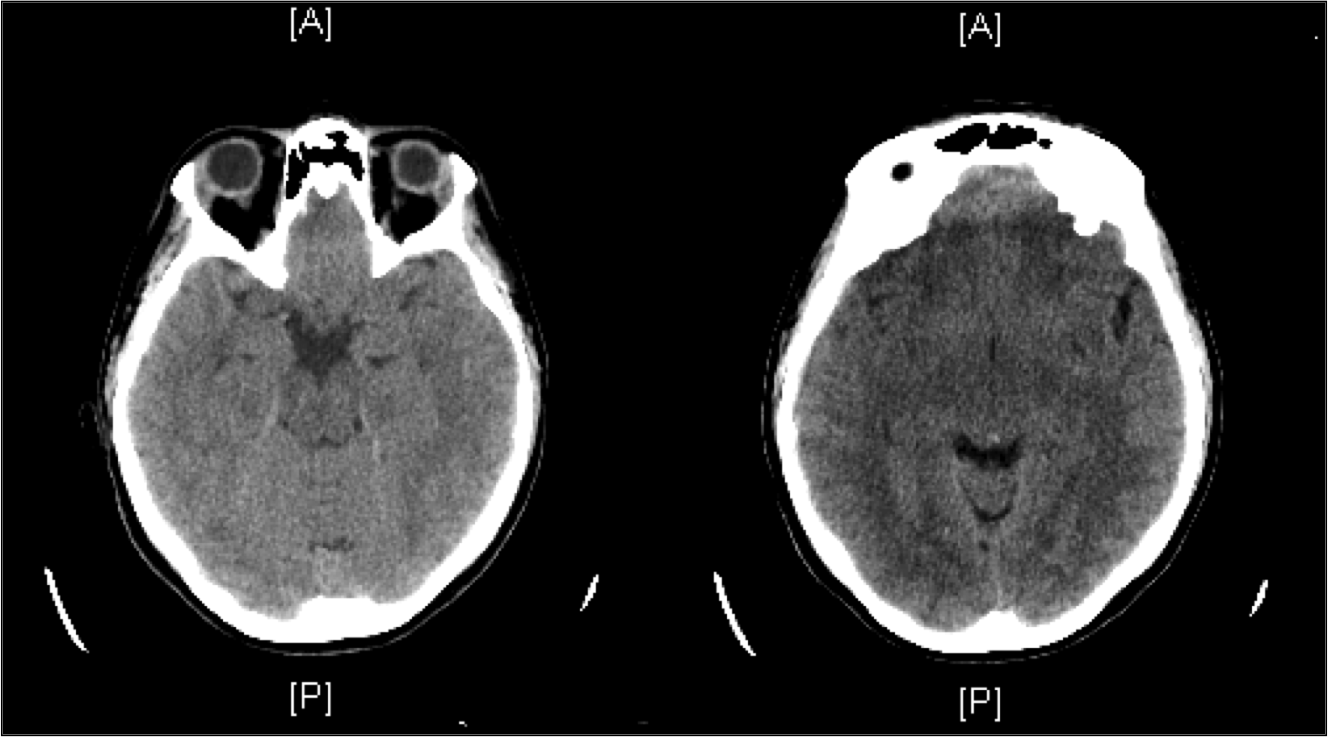

Esta semana Cristina Torregrosa, del Servicio de Microbiología del Hospital Universitario Son Espases, nos presenta el caso clínico de una paciente de 30 años que acude a urgencias por cefalea y fiebre, esperamos que os animéis a participar en el mismo.

Presentación del caso clínico